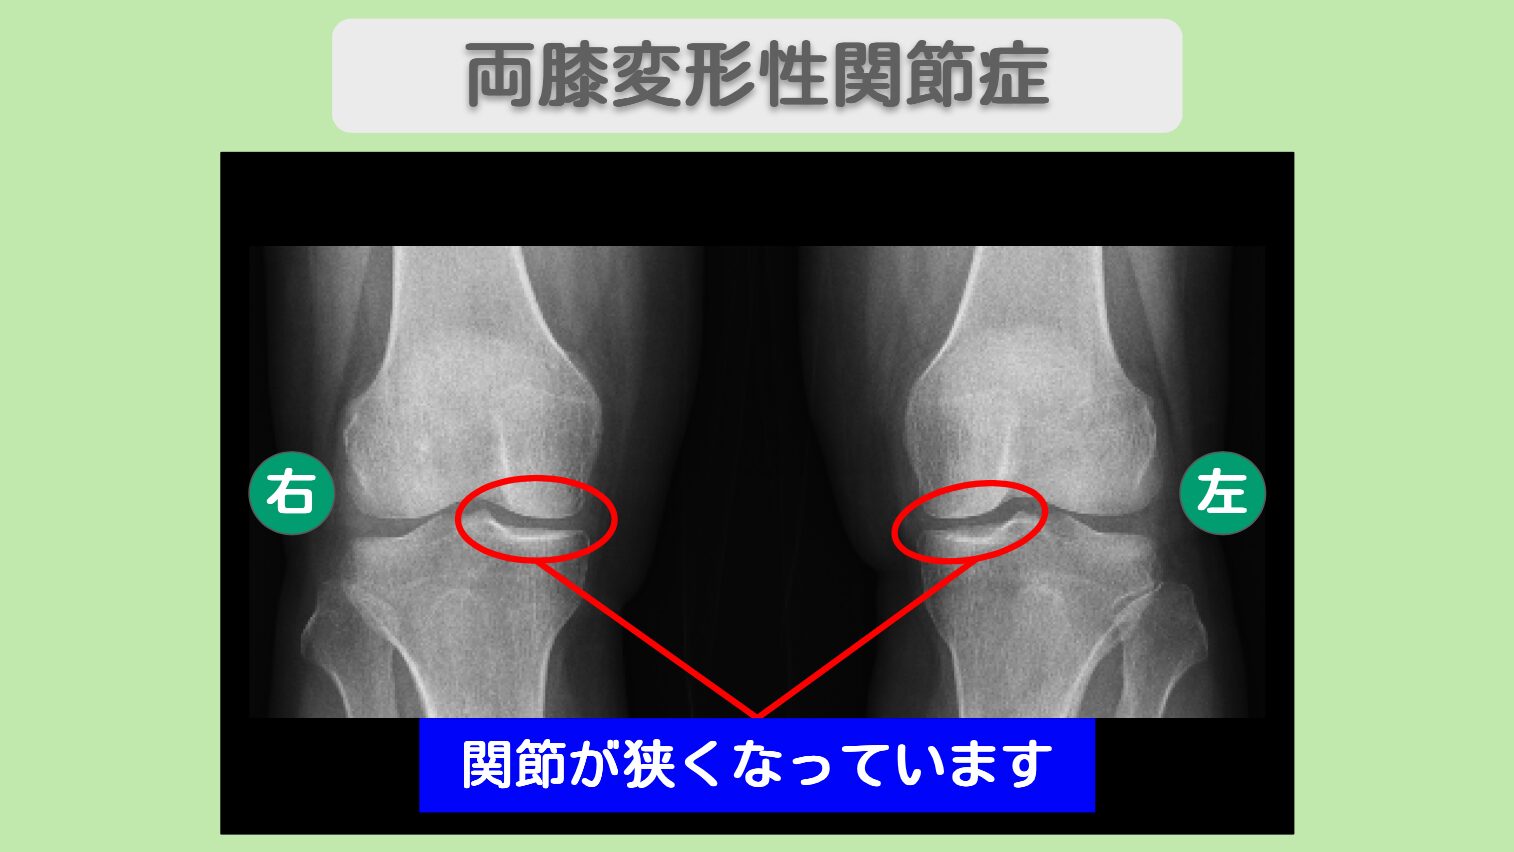

レントゲン所見

<治療内容>右膝に3500万個、左膝に1500万個細胞を計3回投与+PRP

右膝に3500万個、左膝に1500万個の幹細胞を計3回投与いたしました。